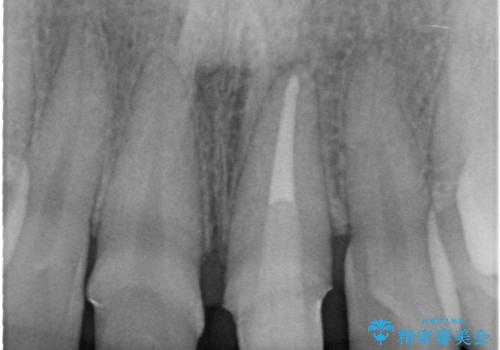

左上の前歯がわずかに短いことを気にされていたため、歯周外科にてこれを可及的に改善し、セラミックにて修復を行いました。

セラミックの種類:PFZ standard

今回は、仮歯の状態で歯の長さを調整する歯周外科をおこなう

→歯茎の治りを待っている間、根管治療のやり直しを行う

→土台を築造しセラミックを完成させる

ことで前歯を残し、長さが揃うようにしました。